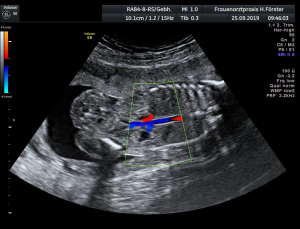

Gynäkologische Grundversorgung Frauenärztliche Krebsfrüherkennungsuntersuchung Nachsorge und supportive Therapie bei bösartigen gynäkologischen Tumoren Impfungen Brustultraschall Ultraschalluntersuchung der weiblichen Genitalorgane Psychosomatische Grundversorgung Chlamydienscreening FOB-Test (früher Hämoccult) Kontrazeption Geburtshilfliche Grundversorgung Geburtshilflicher Basisultraschall Erweiterter Basisultraschall (Organscreening) zw, 18-22.SSW Doppler/Duplexsonografie des fetomaternalen Gefäßsystems Infektionsscreening in der Schwangerschaft CTG (Kardiotokographie) Gynäkologische Grundversorgung Dies umfasst die Abklärung und Behandlung gynäkologischer Erkrankungen. Eine große Rolle dabei spielt das ärztliche Gespräch, ergänzt bei Notwendigkeit durch die gynäkologische Untersuchung oder Untersuchung der weiblichen Brust. In vielen Fällen werden noch Zusatzuntersuchungen durchgeführt (z.B. Ultraschalluntersuchungen, Abstrichentnahmen, Blutentnahmen) oder weiterführende Untersuchungen veranlasst (z.B. Röntgenuntersuchungen). >> zurück << Frauenärztliche Krebsfrüherkennungsuntersuchung Die Krebsfrüherkennungsuntersuchung der Frau ist wahrscheinlich die bekannteste Leistung unseres Fachgebietes. Ab dem Alter von 20Jahren hat jede Frau ein Anrecht auf diese jährliche Untersuchung. Dabei werden der Unterleib der Frau und ab dem Alter von 30Jahren auch die Brüste der Frau systematisch klinisch untersucht. Zusätzlich erfolgte seit vielen Jahren ein Pap-Abstrich vom Gebärmutterhals. So konnten Zellveränderungen meist rechtzeitig erkannt und behandelt werden und es wurde erreicht, daß das früher sehr häufige Zervixkarzinom (Gebärmutterhalskrebs) heute nur noch selten auftritt. Um die Qualität weiter zu verbessern erfolgte 2020 eine Neuordnung des Screenings mit Überarbeitung der Abstrichintervalle und Hinzunahme von HPV-Abstrichen ab 35 als Kassenleistung. >> zurück << Nachsorge und supportive Therapie bei bösartigen gynäkologischen Tumoren Nach Abschluss und oft auch wärend der Primärbehandlung können Probleme auftreten. Es macht also Sinn, sich in regelmäßigen Abständen zu treffen, um das weitere Vorgehen zu planen, eventuell Zusatzuntersuchungen zu veranlassen oder zusätzlich wegen der Beschwerden zu behandeln. Die Nachsorgeuntersuchungen finden anfangs engmaschig statt, später werden die Intervalle länger. >> zurück << Impfungen In Zeiten der Globalisierung, zunehmender Reisefreudigkeit und Zuwanderung werden wir wieder mit Infektionserregern konfrontiert, die wir schon als besiegt geglaubt hatten. Gleichzeitig werden wir immer älter und unser Immunsystem dabei nicht besser. Es reicht nicht, mal eben alle 10Jahre Tetanus zu impfen. Sind Sie geschützt? Wissen Sie was empfohlen ist? Bringen Sie den Impfausweis (auch den alten!!) mit. Wir prüfen Ihren Impfstatus, geben Ihnen Empfehlungen. Die gängigsten Impfstoffe haben wir auch vorrätig und können Sie impfen. >> zurück << Brustultraschall Die Ultraschalluntersuchung der Brust (Mammasonografie) kommt zur Abklärung von krankhaften Veränderungen zur Anwendung oder als Zusatzuntersuchung in der Früherkennung von Brustkrebs bei sehr dichtem Gewebe oder familiärer Vorbelastung. Sie ersetzt nicht das organisierte Mammographiescreening und ist nicht Bestandteil der normalen Krebsfrüherkennung. Es handelt sich um eine schmerzfreie Untersuchung ohne Strahlenbelastung. Die Mammasonografie  ist auch als Wunschleistung (IGeL) möglich. >> zurück << Ultraschalluntersuchung der weiblichen Genitalorgane Die Ultraschalluntersuchung der weiblichen Genitalorgane kommt zur Abklärung von krankhaften Veränderungen des weiblichen Genitales zur Anwendung. Dabei werden mit einer hochfrequenten Vaginalsonde die Organstrukturen im kleinen Becken untersucht. Die Untersuchung ist bei schlanken und sehr jungen Frauen auch vom Bauch aus möglich, die Genauigkeit ist dabei technisch bedingt aber schlechter.  Sie ist nicht Bestandteil der normalen Krebsfrüherkennung. Auch diese Untersuchung ist als Wunschleistung (IGeL) möglich. >> zurück << Psychosomatische Grundversorgung Jede Erkrankung belastet die Seele. Eine seelische Belastung macht den Körper krank. Jeder weiß das. Die Zusammenhänge zwischen dem kranken Körper und der kranken Seele beschreibt die Psychosomatik. Ein "Gordischer Knoten", der nur schwer zu zerschlagen ist, oft ein langer Weg. Ziel ist es, diese Zusammenhänge zu erkennen und den Betroffenen zu helfen ihren Weg zu finden. Oft ist die Zusammenarbeit mit einer Psychologin/ Psychologen nötig. Wichtig ist die Hilfe bei den ersten Schritten. Laufen müssen Sie selbst. >> zurück << Chlamydienscreening Das Bakterium Chlamydia trachomatis kann beim Sex übertragen werden und zu Entzündungen und sogar zur Unfruchtbarkeit führen. Deshalb bezahlen die Krankenkassen bis zum vollendeten 25.Lebensjahr allen sexuell aktiven Frauen einen Suchtest auf Chlamydien. Sie müssen lediglich eine Urinprobe abgeben. Auch in jeder Schwangerschaft wird nach Chlamydien gefahndet. Da Frauen im Normalfall auch im Alter über 25Jahren sexuell aktiv sind und noch schwanger werden wollen bieten wir die Testung auch als Wunschleistung (IGeL) an. Der Test wird dann aus einem Abstrich aus dem Muttermund entnommen, dies kann bei der Krebsfrüherkennung mit gemacht werden. >> zurück << FOB-Test (früher Hämoccult) Im Alter von 50 bis 54Jahren bezahlen die Krankenkassen allen versicherten Frauen einen Stuhltest zur Früherkennung von Darmkrebs oder seiner Vorstufen. Mit 55Jahren können Sie sich entscheiden zwischen zwei Darmspiegelungen im Abstand von 10Jahren oder der Fortführung der Stuhlteste alle 2Jahre. Natürlich kann man Stuhlteste auch zwischen den Darmspiegelungen machen lassen oder auch bei Frauen jünger als 50. Wir bieten dies als Wunschleistung (IGeL) unseren Patienten an. >> zurück << Kontrazeption Ein selbstbestimmtes Leben als Frau ist bei uns in Deutschland eine Selbstverständigkeit. Das war nicht immer so.  Kinder-Küche-Kirche hieß es früher, damals, in der guten alten Zeit. Das ist zum Glück vorbei. Und begonnen hat alles mit der Pille. Frauen konnten endlich über ihren Körper selbst bestimmen, ohne Angst ihre Liebe leben.  Aber die Pille ist nicht alles. Viele Märchen sind im Umlauf, Fehlinformation. Aber auch fehlendes Wissen zu Risiken.  Wir beraten Sie gern. >> zurück << Geburtshilfliche Grundversorgung In der Schwangerenberatung werden die werdenden Muttis gemäß den geltenden Mutterschaftsrichtlinien vom Anfang der Schwangerschaft bis zur Abschlussuntersuchung (6-8 Wochen nach der Geburt) betreut. >> zurück << Geburtshilflicher Basisultraschall Nach Vorgabe der Mutterschaftsrichtlinie sind sind in der Schwangerschaft 3 Ultraschalluntersuchungen vorgesehen. Diese finden in der 8.-12. SWW, in der 18,- 22. SSW und in der 28.-32.SSW statt. Dabei werden der Zustand des Embryos/ Feten, des Fruchtwassers und der Plazenta beurteilt. >> zurück << Erweiterter Basisultraschall (Organscreening) zw. 18-22.SSW Bei der zweiten Ultraschalluntersuchung (zw.18.-22. SSW) erfolgt ein erweitertes Screening mit Beurteilung der Organstrukturen des Kindes. Diese Untersuchung ist Kassenleistung, kann aber bei Wunsch auch Abgewählt werden, dann wird nur der Basisultraschall durchgeführt. >> zurück << Doppler/Duplexsonografie des fetomaternalen Gefäßsystems Bei Aüffälligkeiten im Schwangerschaftsverlauf oder auch bei bestimmten Vorerkrankungen oder Erkrankungen in einer früheren Schwangerschaft kann es notwendig sein die Durchblutung des Mutterkuchens und der Gefäße des Kindes zu Untersuchen. Hier kommt das Dopplerverfahren als Erweiterung des normalen geburtshilflichen Ultraschalls zum Einsatz. Dies erlaubt eine schnelle Zustandsbeurteilung des Kindes pepaart mit einer zeitlich begrenzten Vorhersage über die weitere wahrscheinliche Entwicklung. Bei entsprechender Indikation ist diese Untersuchung als Kassenleistung abrechenbar. >> zurück << Infektionsscreening in der Schwangerschaft Die Suche nach Krankheitserregern im Krankheitsfall ist Kassenleistung. Routinemäßig prüfen wir Ihren Schutz vor Röteln und Windpocken , in jeder Schwangerschaft erfolgt ein Test auf Chlamydien. Zusätzlich empfehlen wir jeder Schwangeren einen Test auf eine Besiedelung mit Gruppe-B-Streptokokken vor der Geburt. Diese Streptokokken können zu schweren Atemwegsinfektionen des Neugeborenen führen. Eine vorbeugende Behandlung bei positivem Test kann dann unter der Geburt erfolgen. Bei Wunsch kann auch ein erweitertes Erregerscreening über unser Labor erfolgen (Wunschleistung). Eine wichtige Rolle spielt auch die Kontrolle auf einen Schutz gegen eine Toxoplasmoseinfektion. Bei fehlendem Schutz empfielt sich die regelmäßige Testung aus dem Blut auf eine frische Infektion. Auch dies ist eine Privatleistung, wird aber von den meisten Kassen erstattet. Eine nicht erkannte und somit nicht behandelte Erstinfektion in der Schwangerschaft kann zu schweren Schäden beim Kind führen. >> zurück << CTG Ab etwa der 30.Schwangerschaftswoche können wir bei Notwendigkeit im Ramen der Schwangerschaftsvorsorge die kindlichen Herztöne (Kardiographie) und simultan dazu die die Spannung der mütterlichen Bauchdecke (Wehenschreiber, Tokographie) graphisch darstellen. Das nennt man zusammen Kardiotokographie oder kurz einfach CTG. Die Auswertung des CTG‘s erfolgt nach dem Fisher-Score (Punkte-System) sowie nach qualitativen Kriterien und erlaubt uns eine gute Zustandsbeurteilung des Kindes in den späteren Schwangerschaftswochen. >> zurück <<